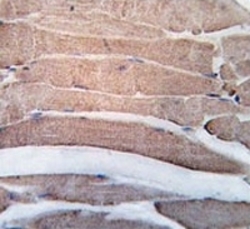

Supportive validation

- Submitted by

- NSJ Bioreagents (provider)

- Main image

- Experimental details

- IHC testing of FFPE human skeletal muscle tissue with Death-associated protein kinase 2 antibody. HIER: steam section in pH6 citrate buffer for 20 min and allow to cool prior to staining.